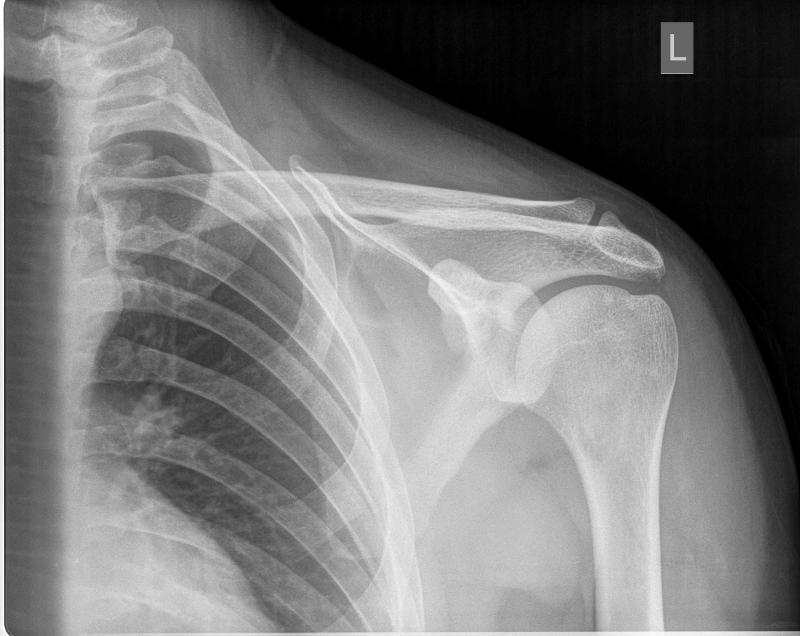

5. What exam is this and what is it checking for and how can you tell what it is?

Y view, you can tell because the vertebral border of scapula and it is checking for dislocation of humerus.